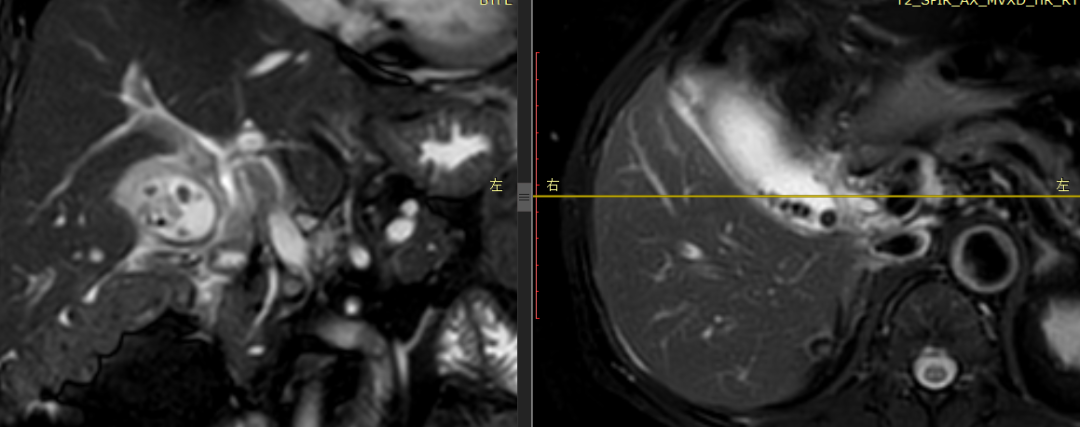

CASE 3